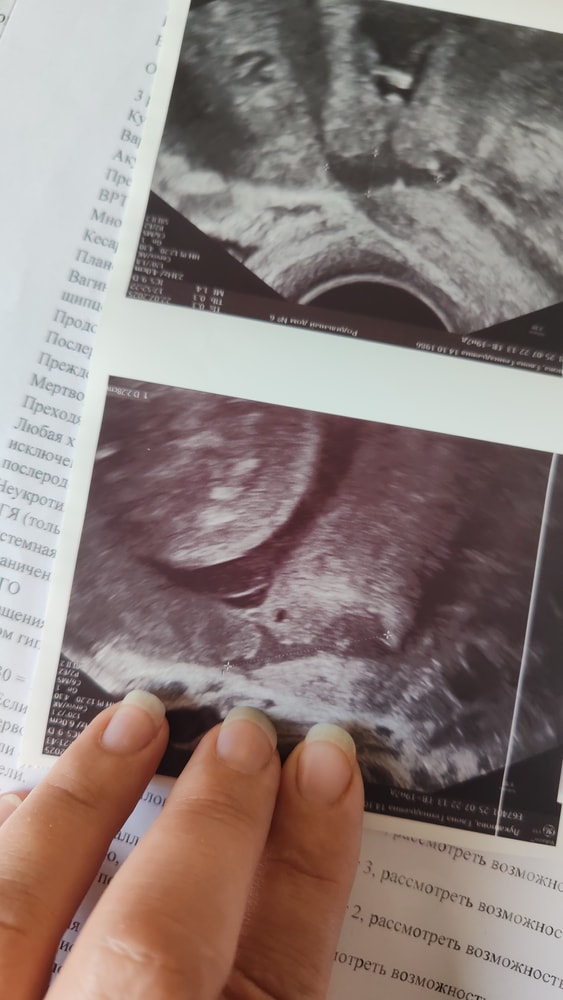

Всё о рубцеСъездила 22го на 2 скрининг. Перед скринингом заехала в Перинатальный центр Педиатрического Института. С направлением по тонкому рубцу на отборочную комиссию. Там сказали, что с толщиной около 1мм и менее могут провести лапаротомию на беременную матку, те прооперировать и наложить новый шов на старый рубец, чтоб доносить было больше шансов. Но это все звучит как-то очень страшно для меня пока. Отпустили на скрининг, чтоб там ещё раз на узи измеряли рубец. Результат оказался таким же : 1,3мм в самом тонком месте ниши, 1,8мм с другого бока. Ниша не маленькая, длина более 22мм. Ставят несостоятельность рубца под вопросом, узист рекомендует МРТ рубца.Повторно в Перинатальный ещё не ездила, думаю пока, как лучше поступить, собираю информацию и отзывы.

Пугает меня мысль об операции с плодом внутри, наркоз ещё, да и реабилитация потом долгая... Все же это тоже кесарево, но ещё и на беременную матку...Подробнее: рубец 1,2-1,3 мм с 12 недель, сейчас 20я неделя. Держится пока, не истончается, но есть довольно не маленькая ниша...Девочки, кто был в подобных ситуациях, что посоветуете? Тянуть и наблюдать, или рисковать и резать🫣?